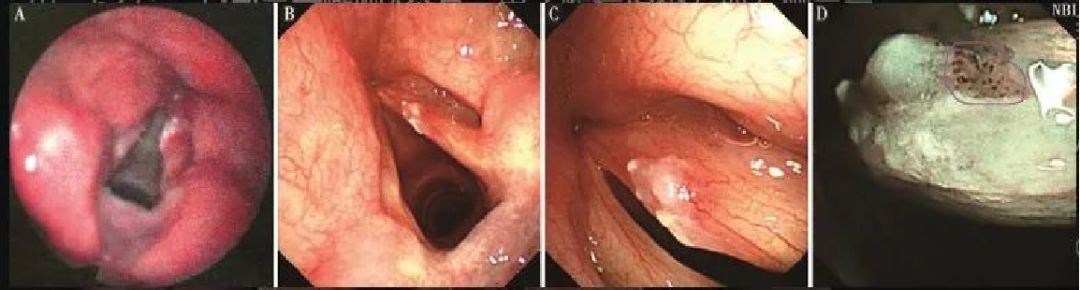

喉部早期癌

喉部结构基本完整,会厌及左、右披裂黏膜基本光滑,普通光下很难发现声带病变。NBI模式下可见IPCL扩张形成典型的斑点状表现。病变累及左侧声带近全长,向前累及并跨越前联合,侵达右侧声带前端约1/3。